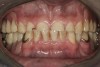

Initial examination revealed a partial edentulous patient with extensive wear of the maxillary anterior teeth and moderate wear in the mandibular teeth (Figure 1, Figure 2, Figure 3, Figure 4, Figure 5, Figure 6 and Figure 7). The patient’s maxillary and mandibular RPDs also showed excessive wear and multiple signs of fractures (Figure 2 and Figure 3). The patient had been wearing a mandibular nightguard for 8 years.

Figure 1  Intraoral anterior view of the patient presenting a severely worn maxillary dentition and loss of OVD.

Figure 1